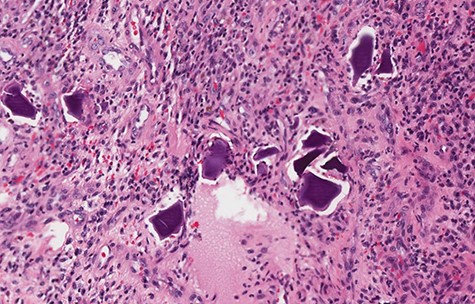

Fifty centimeters of diseased ileum that consisted of multiple strictures and adhesions was resected and a double barrel ileostomy was formed for antegrade colonic vancomycin lavage. The patient had an uneventful recovery. Pathology of the specimen revealed necrosis in the small bowel segment along with a full thickness ulcer with granulation tissue, consistent with an ischemic type injury pattern. SPS crystals were identified within the granulation tissue despite no record of SPS administration more recently than 1 year prior for hyperkalemia (Fig. 1).

Small bowel biopsy revealing SPS crystals in intestinal mucosa with inflammatory changes.